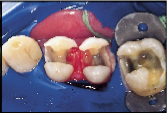

However, many of our restorative options are limited by patients financial situation. In cases where patients are forced to forego an ideal indirect restoration, a well-placed, less than ideal direct composite resin may be the best compromise treatment if they are seeking a non-metallic restoration (Figs. 4a and 4b). Consider the depth and width of the lesions of the three maxillary teeth in Fig. 4a. These teeth would be best restored with an indirect option subsequent to the appropriate gingival relocation. Nevertheless, for this patient who requested a tooth-coloured restoration, the challenge was met with innovative procedural manipulations and the diligent application of basic adhesive principles. Sometimes a compromise treatment is the best option in particular circumstances, as long as the decision is reached jointly by the dentist and patient and the latter is informed of all reasonable options.7 In this instance, the patient now has the opportunity to use an indirect approach in approximately eight years time when the restorative margins begin to break down. Without the direct intermediate treatment, the teeth may have been further structurally compromised by the expanding and leaking cariously undermined alloys. (It is not the authors intention to disparage the adhesive process but rather to put restorative expectations in perspective so that the appropriate level of clinical diligence can be maintained. Although improved placement techniques may enhance the performance of current posterior composite resins over their predecessors [ Fig. ], they should still be regarded as a compromised restorative option when applied to extensive lesions.)

| Figure 4a: For patients with limited finances, a well-placed, direct composite resin may be the best compromise treatment if they are seeking a non-metallic restoration | Figure 4b: Post-operative view of restored maxillary sextant. | Figure 5a: A direct composite resin was used for this maxillary first molar since the patient could not afford an indirect solution. | Figure 5b: Esthetics, function and form successfully restored. |